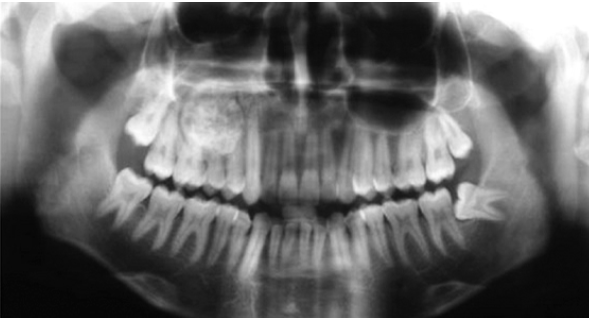

fibrous dysplasia radiographic characteristics

“ground glass” appearance on radiograph

abnormal bone blends into the normal adjacent bone

ill-defined borders